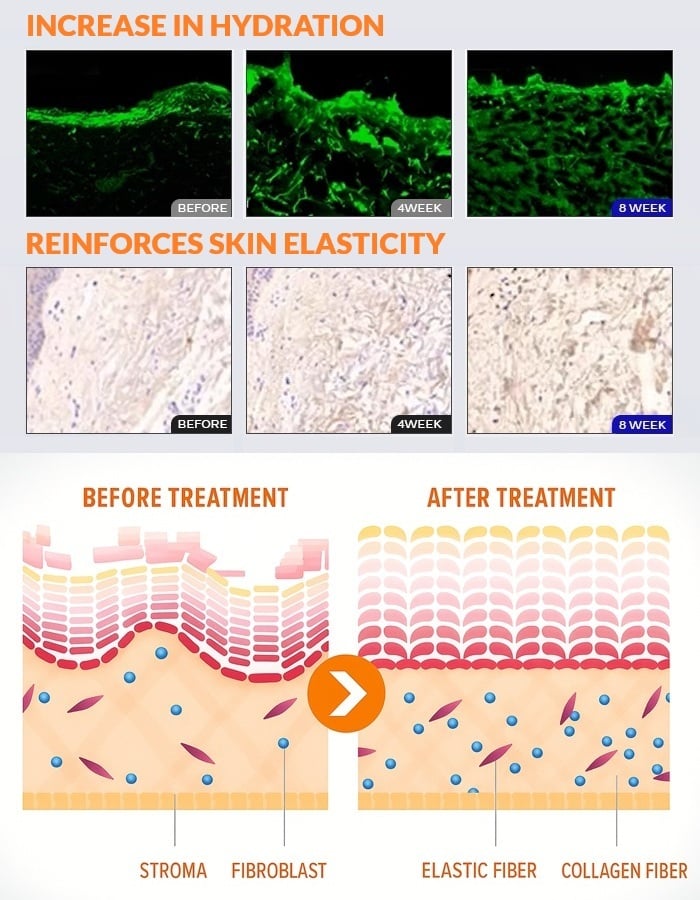

- Boosts Skin Elasticity: Stimulates collagen and elastin production for firmer, more resilient skin.

- Deep Hydration: Delivers lasting moisture to dry, stressed skin.

- Hydrate And Restore The Skin Barrier: Rich moisturizers and infused deep hydration, helping to rebuild the skin’s protective layer and improve suppleness from within.

- Boost Collagen And Skin Elasticity: Support collagen and elastin fiber regeneration, improving firmness and reducing stretch mark visibility.